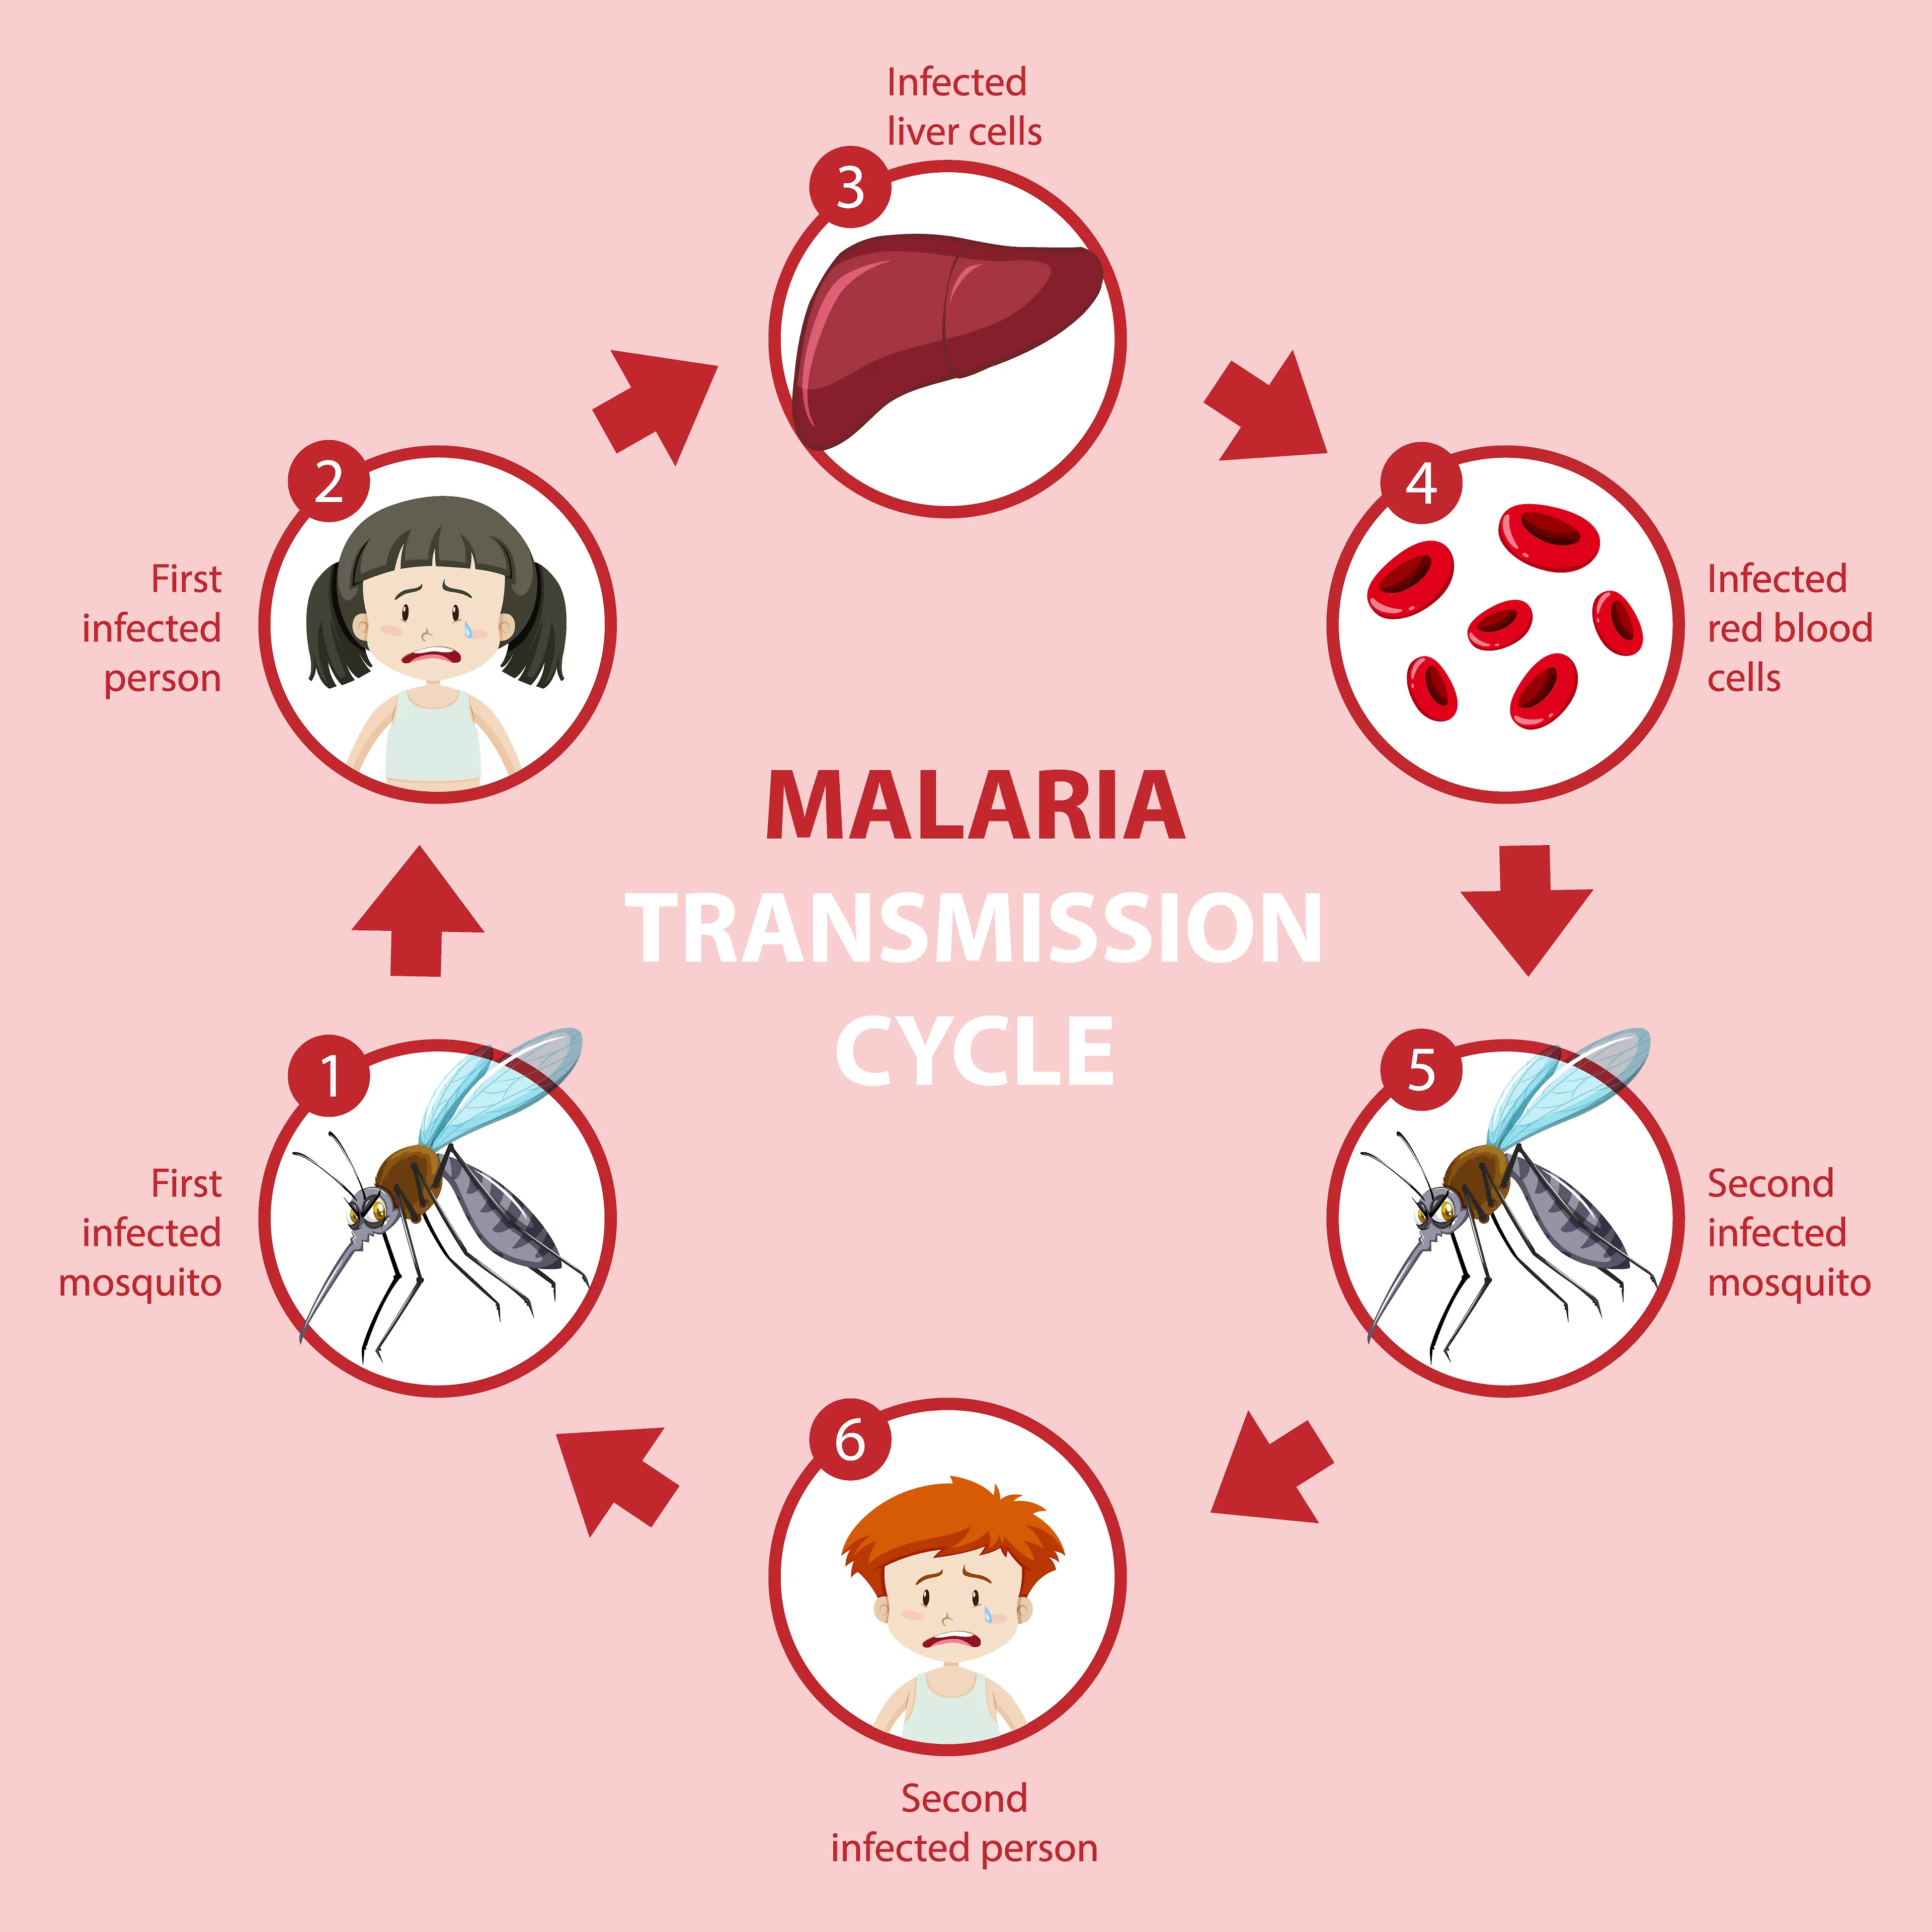

Od malarije godišnje oboli više od 200 milijuna osoba

Zdravstvo-vijesti

25.04.2023